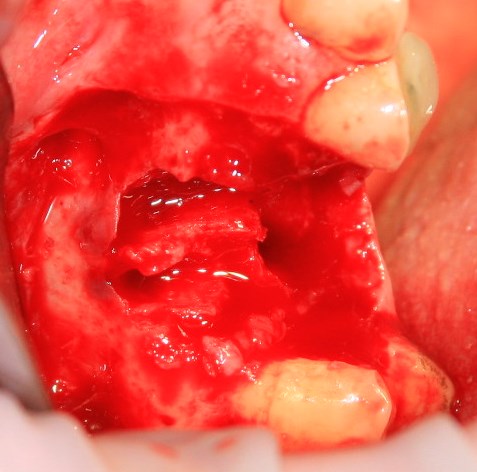

Немедленная имплантация — оптимальное решение в любой клинической ситуации